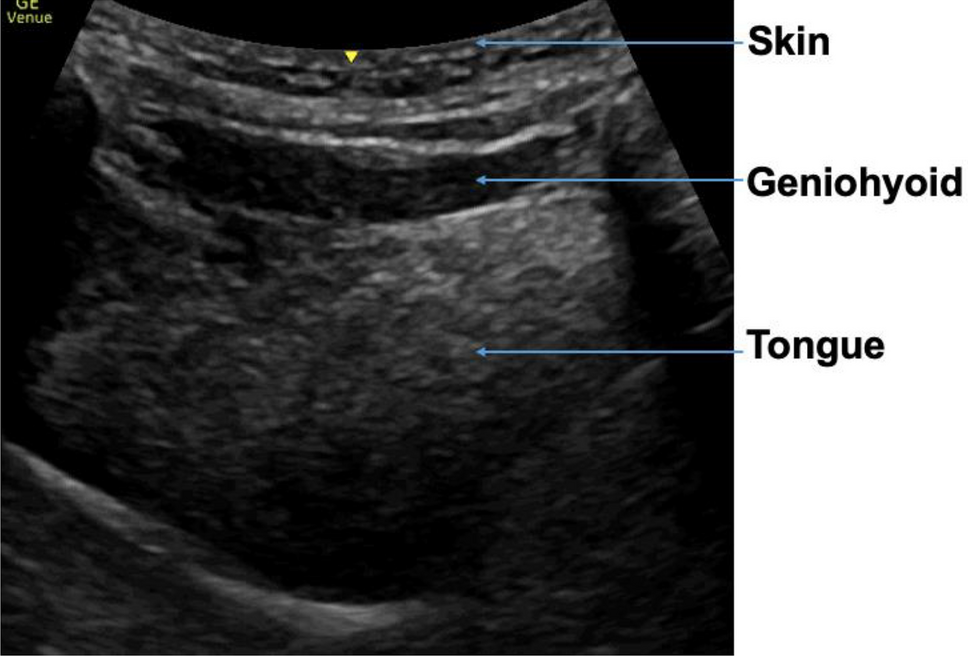

Figure 2

Mass measurements geniohyoid and tongue.